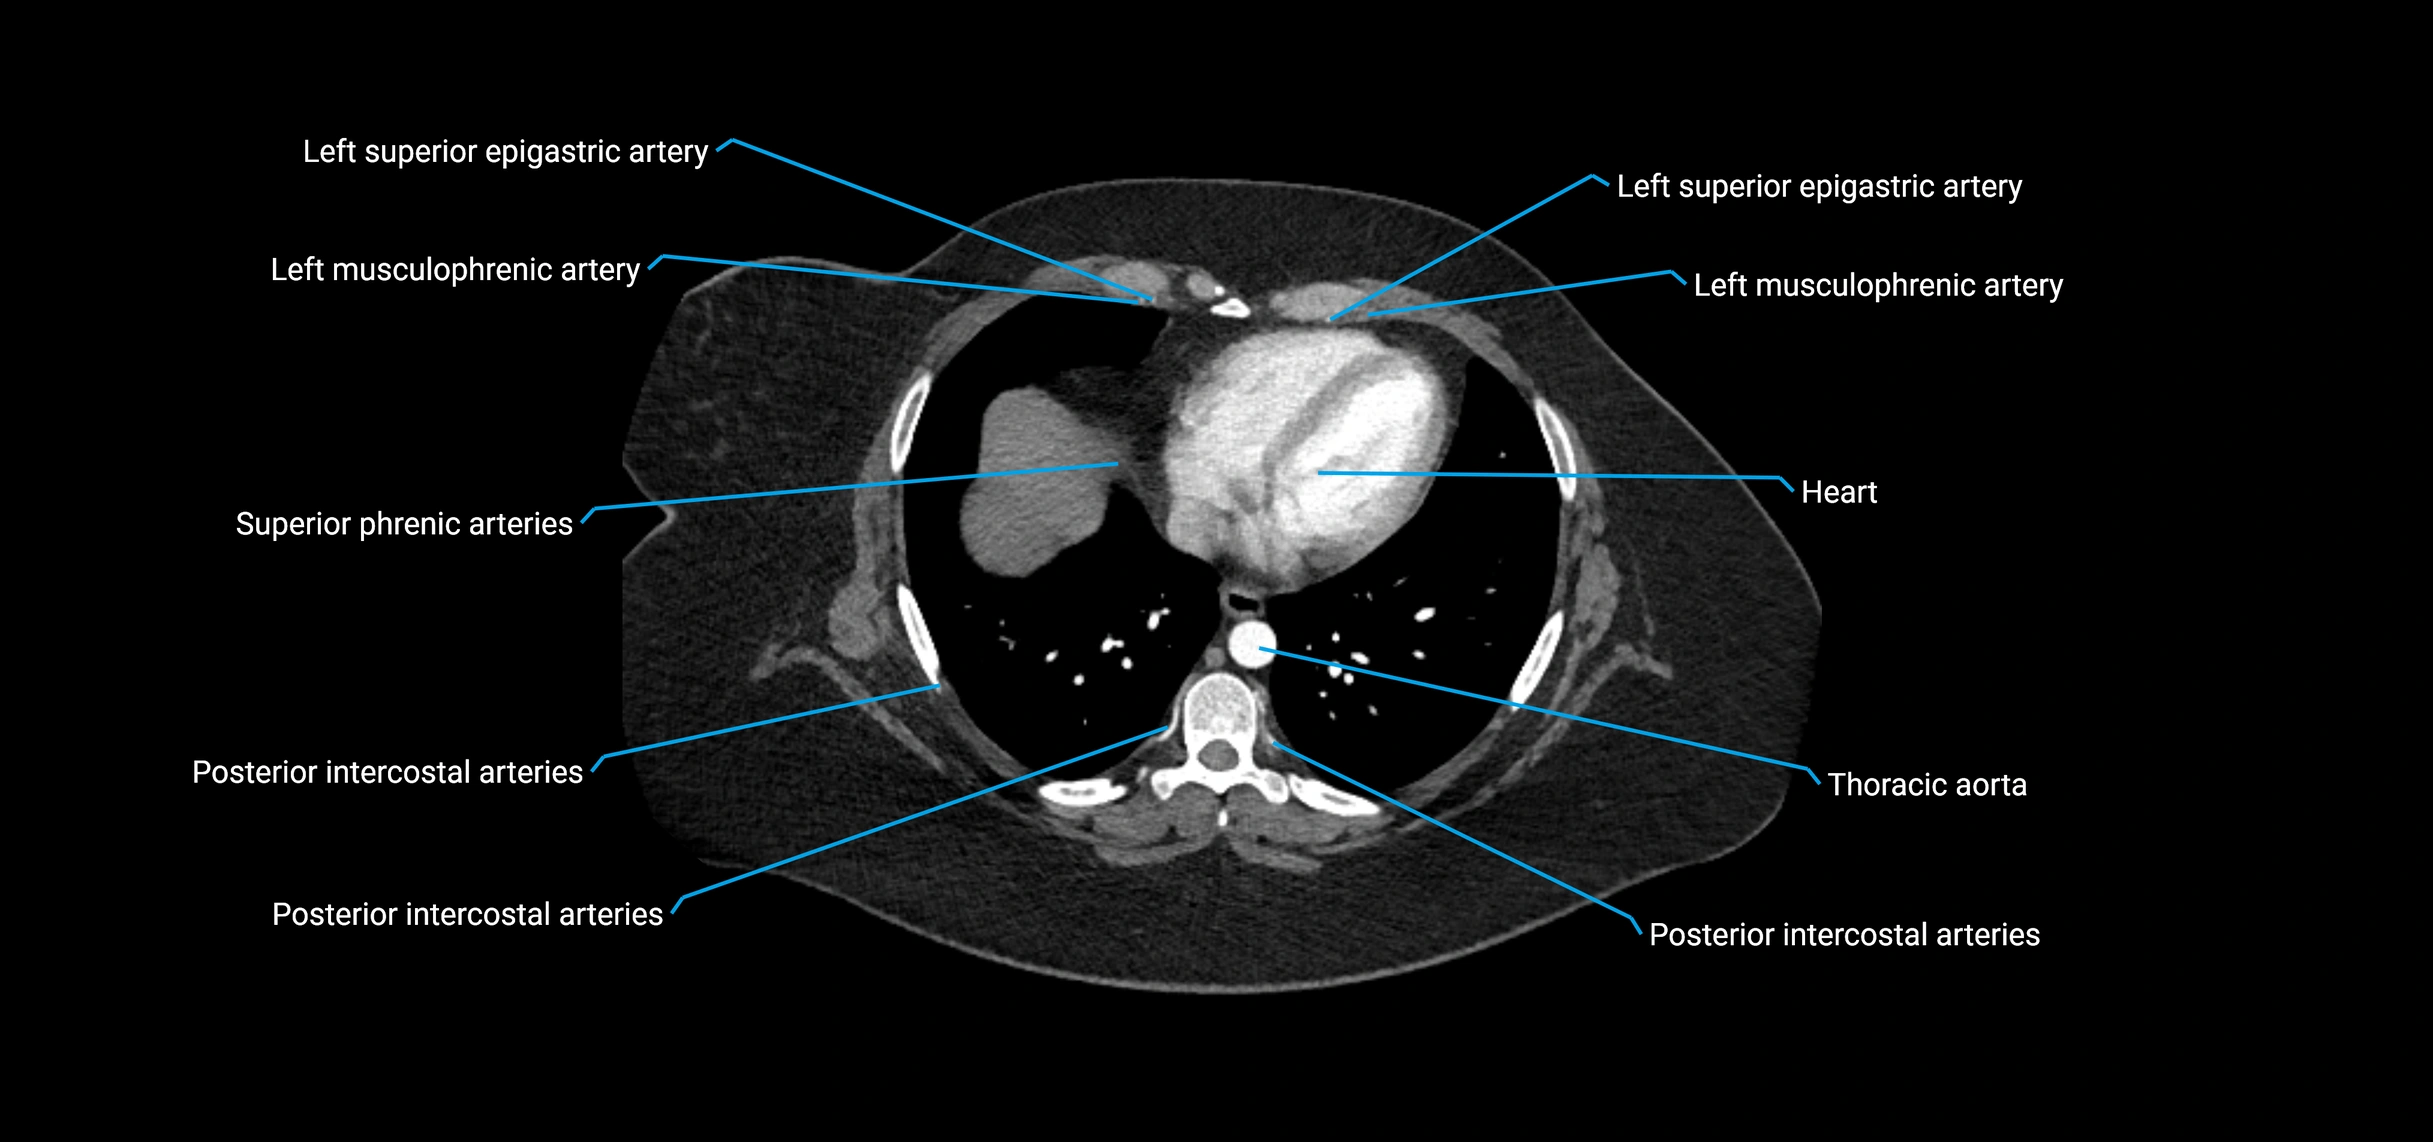

MRI Appearance

T1-weighted images:

• Flowing blood appears as a signal void (black lumen)

• Vessel wall appears as a thin hypointense rim; retroperitoneal fat enhances contrast

T2-weighted images:

• Lumen remains a signal void due to flow

• Adjacent edema, hematoma, or aneurysm wall thrombus may appear hyperintense

T1 Post-Contrast (Gadolinium-enhanced):

• Aortic lumen enhances brightly and homogeneously

• Clearly demonstrates aneurysm, stenosis, dissection, mural thrombus, or aortic wall enhancement in vasculitis

MRA (Magnetic Resonance Angiography):

• Contrast-enhanced MRA provides high-resolution imaging of the aorta and its branches

• Allows 3D reconstruction of visceral, parietal, and terminal branches

• Excellent for evaluating aneurysm size, dissection flap, stenosis, or preoperative planning

• Non-invasive alternative to conventional angiography